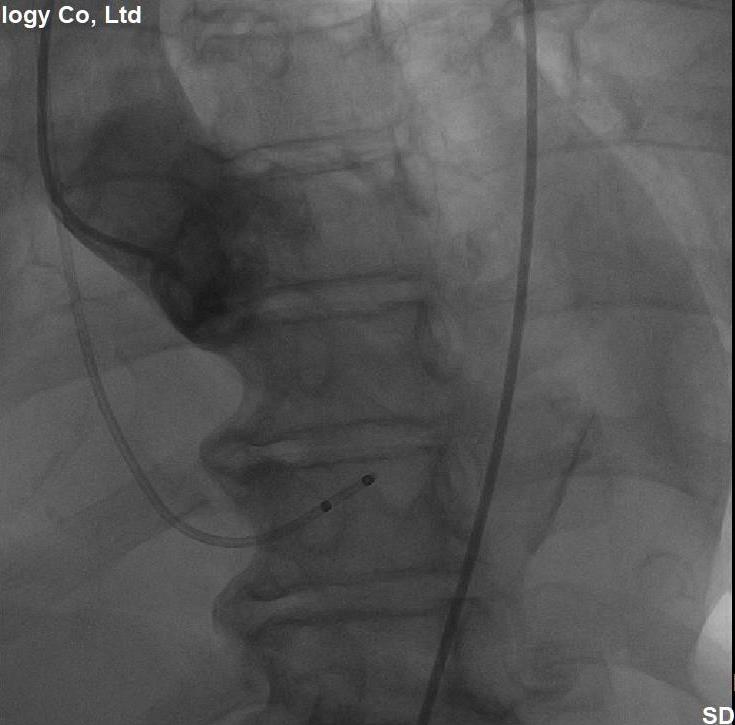

(图3,术中主动脉根部造影,显示主动脉瓣瓣环平面、角度、最佳投照体位)

经过充分细致地准备,多学科积极协作,在张希全主任指导下,心血管外科谷兴华主任医师、急诊心内科李传保主任医师、心血管外科孙厚荣副主任医师及团队成员在绿帽社复合手术室实施手术。根据患者的病情特点,术中做好各种应急预案,备好体外循环,维持血流动力学平稳。根据术前CT分析和术中主动脉根部造影情况(图1、图2、图3),选择最佳投照体位。先选用22mm球囊,临时起搏180次/分,扩张重度狭窄的主动脉瓣(图4)。再选用24mm的介入主动脉瓣膜,造影、定位、临时起搏、顺序释放介入瓣膜,造影及心脏超声检查示:人工瓣膜位置形态满意,瓣膜启闭功能正常,主动脉瓣无瓣周分流,跨瓣压差降至8mmHg(图5、图6)。术后1小时,麻醉清醒,术后8小时顺利脱机拔管,术后第2天转入普通病房,病情稳定,治愈出院。